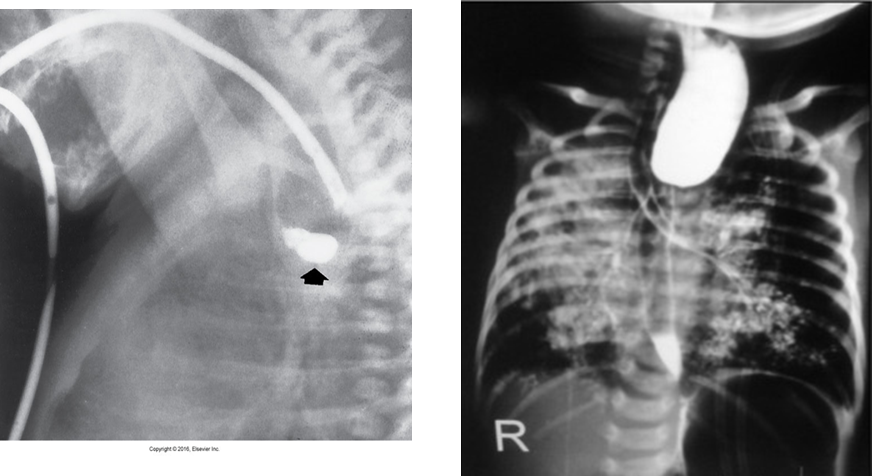

Esophageal Atresia

Is a congenital absence or closure of a normal body orifice or tubular organ.

The lack of the development of the esophageal lumen resulting in a blind pouch.

Caused by defect in cell differentiation of esophagus during 4-6 week of embryonic development.

Symptoms: appear soon after birth as excessive salivation, choking, gagging, dyspnea, cyanosis.

Radiological Appearance:

Tracheoesophageal Fistula

Congenital form – results from the failure of the esophageal lumen to develop completely separate from the trachea.

Acquired type – caused by cancer, infection, trauma, instrumentation perforation.

Radiological Appearance: